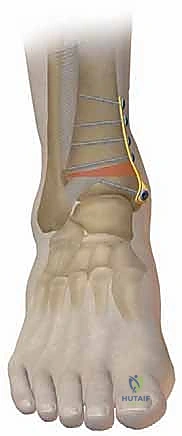

- التعقيم والشق الجراحي: يتم تعقيم الساق بالكامل. يُجري الجراح شقاً جراحياً دقيقاً في الجلد فوق منطقة الكاحل (الجانب الداخلي أو الخارجي حسب نوع القطع). يتم إبعاد الأنسجة الرخوة والأعصاب والأوعية الدموية بحذر شديد لحمايتها.

- قص العظم (Osteotomy): باستخدام منشار جراحي دقيق وموجهات خاصة، يتم قص عظم الظنبوب (وفي بعض الأحيان عظم الشظية أيضاً) بالزاوية التي تم تحديدها مسبقاً في التخطيط الثلاثي الأبعاد.

- التثبيت الداخلي (Internal Fixation): بمجرد الوصول للزاوية المثالية، يتم تثبيت العظم في وضعه الجديد بقوة باستخدام شرائح معدنية متطورة (Locking Plates) ومسامير من التيتانيوم. هذا التثبيت القوي يضمن عدم تحرك العظم أثناء فترة الالتئام.